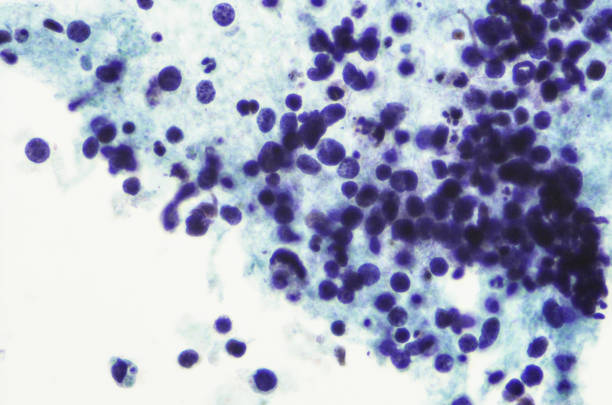

폐암의 초기 증상 5. 객혈

객혈은 또한 폐암의 초기 증상입니다. 암세포가 작아도 기관지를 관통하면 암세포 주변에 수많은 혈관이 생긴다. 폐가 기관지를 자주 자극하면 기침과 가래가 자주 발생하기 때문에 대부분의 폐암 환자들이 통증을 호소하는 것으로 알려져 있다.